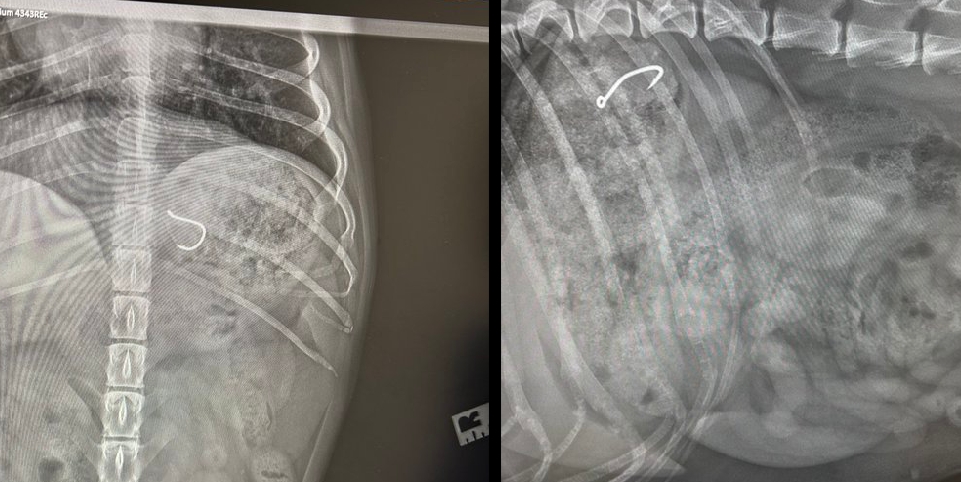

Según ha explicado al Diario de Getxo, se trata del segundo incidente de estas características sufrido por una de sus mascotas, ambos con visita al veterinario incluida. En el primer caso, el anzuelo quedó atrapado en la boca del animal, mientras que en esta ocasión el objeto ha llegado hasta el estómago.

Actualmente, la perra permanece bajo supervisión veterinaria a la espera de comprobar si puede expulsar el anzuelo de forma natural. En caso contrario, será necesaria una intervención quirúrgica, según ha indicado el propio Andrade.